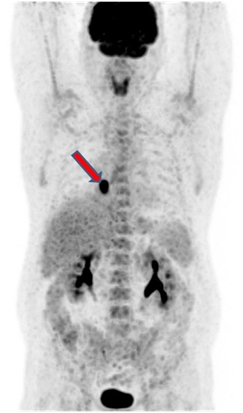

ПЭТ/КТ от 31.05.2017. Отмечается положительная динамика в виде нивелирования центрально расположенного образования нижней доли правого легкого и медиастинального лимфоузла. Постлучевой фиброз, ателектаз нижней доли правого легкого. Умеренно выраженный правосторонний гидроторакс. Повышение метаболизма в кардиальном отделе пищевода – постлучевой воспалительный процесс.

ПЭТ/КТ 04.08.2017. На момент исследования по данным ПЭТ/КТ с 18F-ФДГ признаков патологического метаболически активного процесса, обусловленного основным заболеванием не выявлено.

Постлучевой фиброз, ателектаз нижней доли правого легкого.

Умеренно выраженный правосторонний гидроторакс (увеличение в динамике).